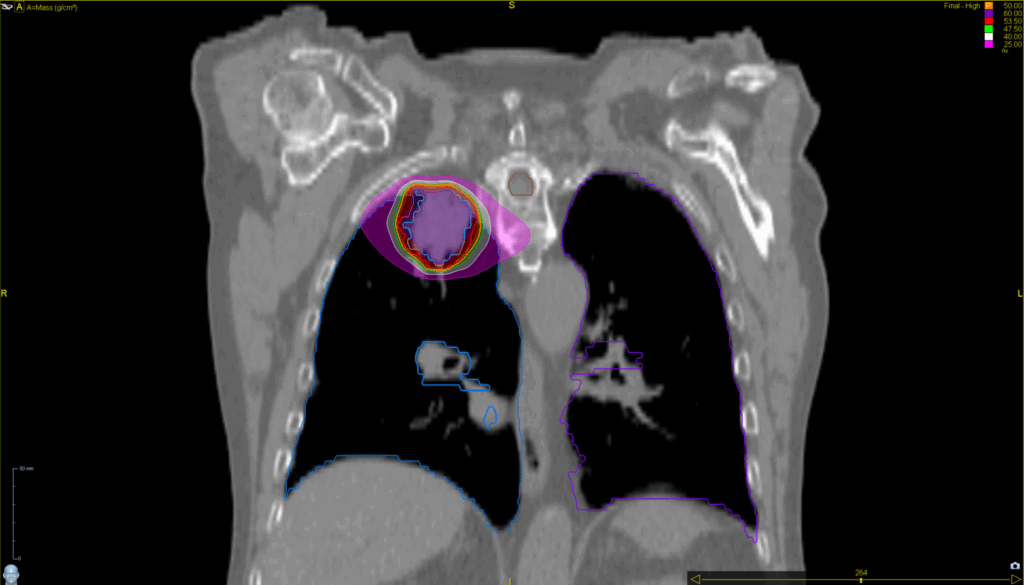

Treatment Plan Images

Fractionation / Protocol Used

50 Gy in 5 fractions

PTV(s) Volume

5 cm, 55 cc

Mode

- Tomohelical™

- Synchrony® Lung™

- SBRT

- TomoEDGE™ 2.5 cm